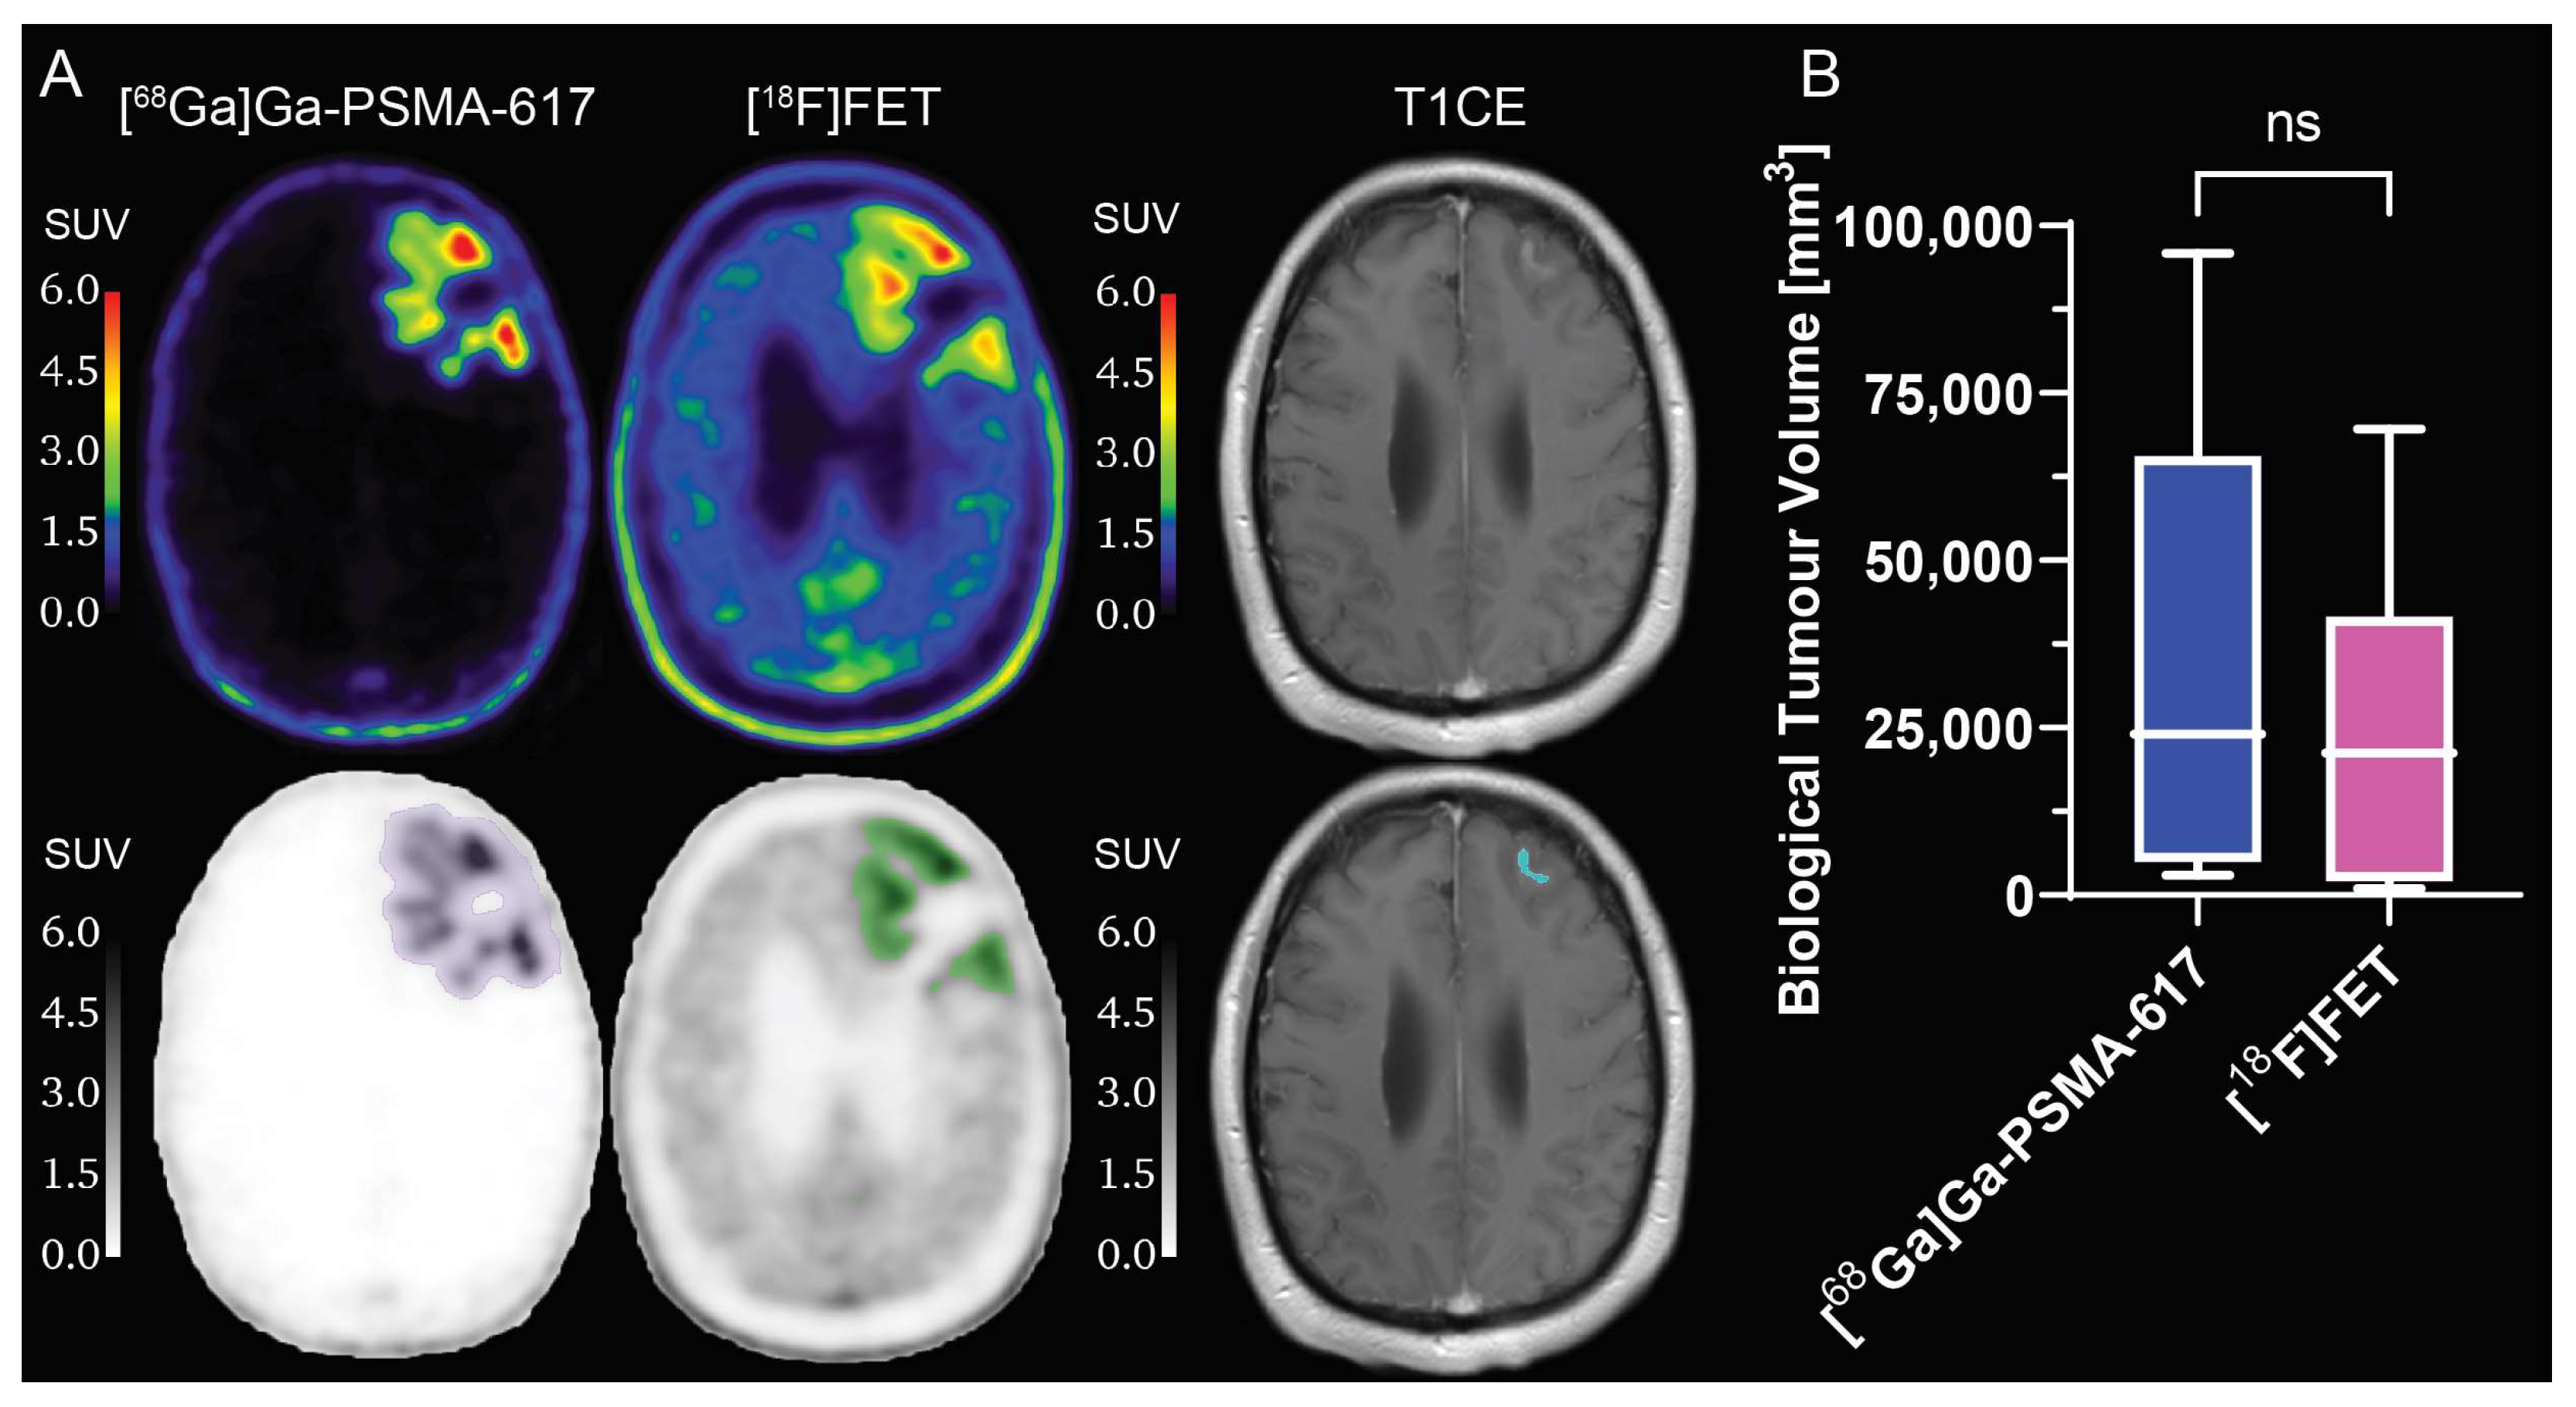

2.2. Evaluation of [68Ga]Ga-PSMA-617 Tumour Selectivity

2.3. Comparison between [68Ga]Ga-PSMA-617 and [18F]FET Tumour Specificity